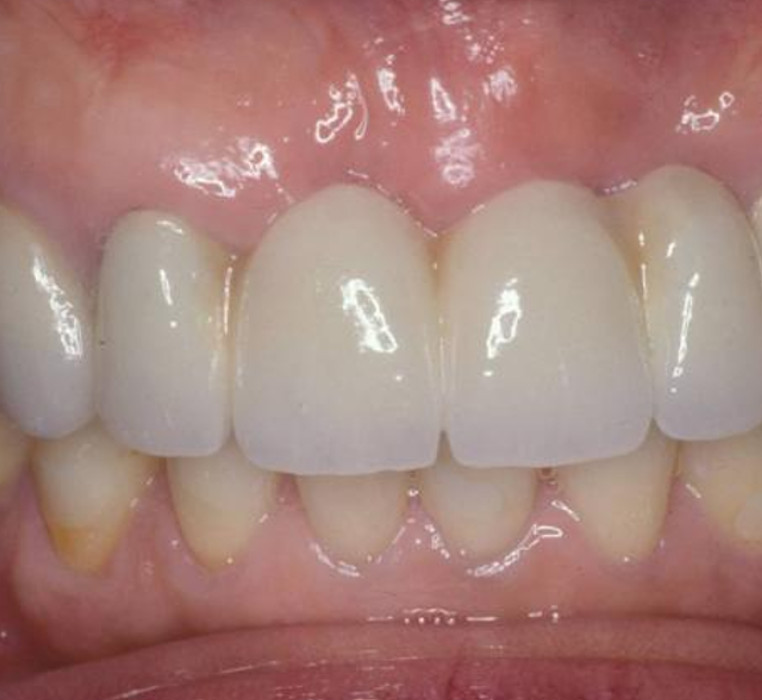

Cosmetic Crown Lengthening

After